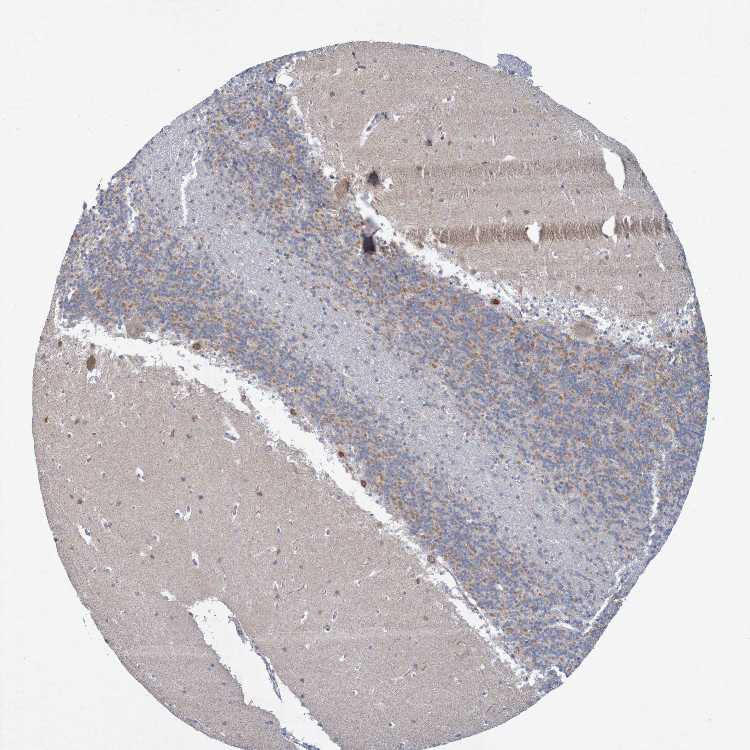

CEREBELLUM - Antibody stainingi

Antibody staining in the annotated cell types in the current human tissue is reported as not detected, low, medium, or high, based on conventional immunohistochemistry profiling in selected tissues. This score is based on the combination of the staining intensity and fraction of stained cells.

Each image is clickable and will lead to virtual microscopy that enables deeper exploration of all samples and also displays staining intensity scores, fraction scores and subcellular localization as well as patient and tissue information for each sample.

Antibody HPA011755Antibody HPA011891

Purkinje cells HighLow

Cells in granular layer LowMedium

Cells in molecular layer Not detectedNot detected